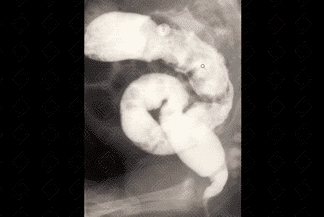

Texto alternativo para a imagem Figura 3. Crédito: Dra. Elazir Mota - Rio de Janeiro/RJ

Descrição das imagens: Clister opaco. Administra-se contraste baritado diluído por sonda retal, seguido da realização de radiografias em AP e perfil. Observa-se, já na fase de enchimento, a desproporção entre calibre do reto e sigmoide, sendo o reto bem menor (figuras 2 e 3). A radiografia simples do abdome em perfil auxilia na suspeição diagnóstica pela não visualização de gás na ampola retal (figura 1).

• Clister opaco: Exame de escolha no quadro de constipação intestinal crônica na população pediátrica. É realizado com paciente na sala de radiografia, com cateterização retal e instilação de contraste baritado diluído por via retal. O contraste deve progredir pelo menos até a flexura esplênica. Seu principal objetivo é afastar a possibilidade de aganglionose colônica, causa cirúrgica de constipação intestinal. Nestes pacientes com aganglinose, observa-se inversão do índice retossigmoideano (reto menor que o sigmoide) e visualização do cone de transição. Podem ser necessárias radiografias tardias - 24 horas após a realização do clister. Importante ressaltar que, no exame normal, o reto deve ter calibre maior ou igual ao do sigmoide.